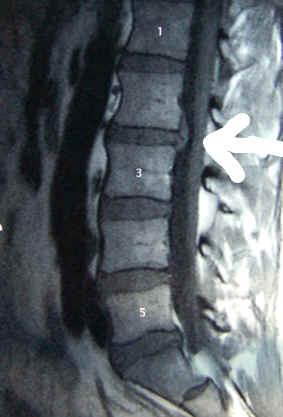

wackeln. Es war relativ warm und es war windig, aber der Grund dafür, dass ich nicht dort war, liegt woanders und zwar genau zwischen zwei Lendenwirbeln. Was das genau bedeutet, wird mir Stephan am Montag wohl

genauer erzählen…

Die gute Nachricht: mit dem Knie und mit der Hüfte ist alles in Ordnung. Die schlechte Nachricht: die Bandscheibe macht Probleme und daher resultierten auch die Schmezen im linken Bein. Weitere Klarheit

wird nun die Kernspin am 31.03. verschaffen, es besteht Verdacht auf Bandscheibenvorfall. Bis dahin müssen Massagen und Fangopackungen helfen. Nun muss sich nur noch die Zeit dafür finden. Am 14.

März ging wohl eine hoffnungsvolle Saison zu Ende...